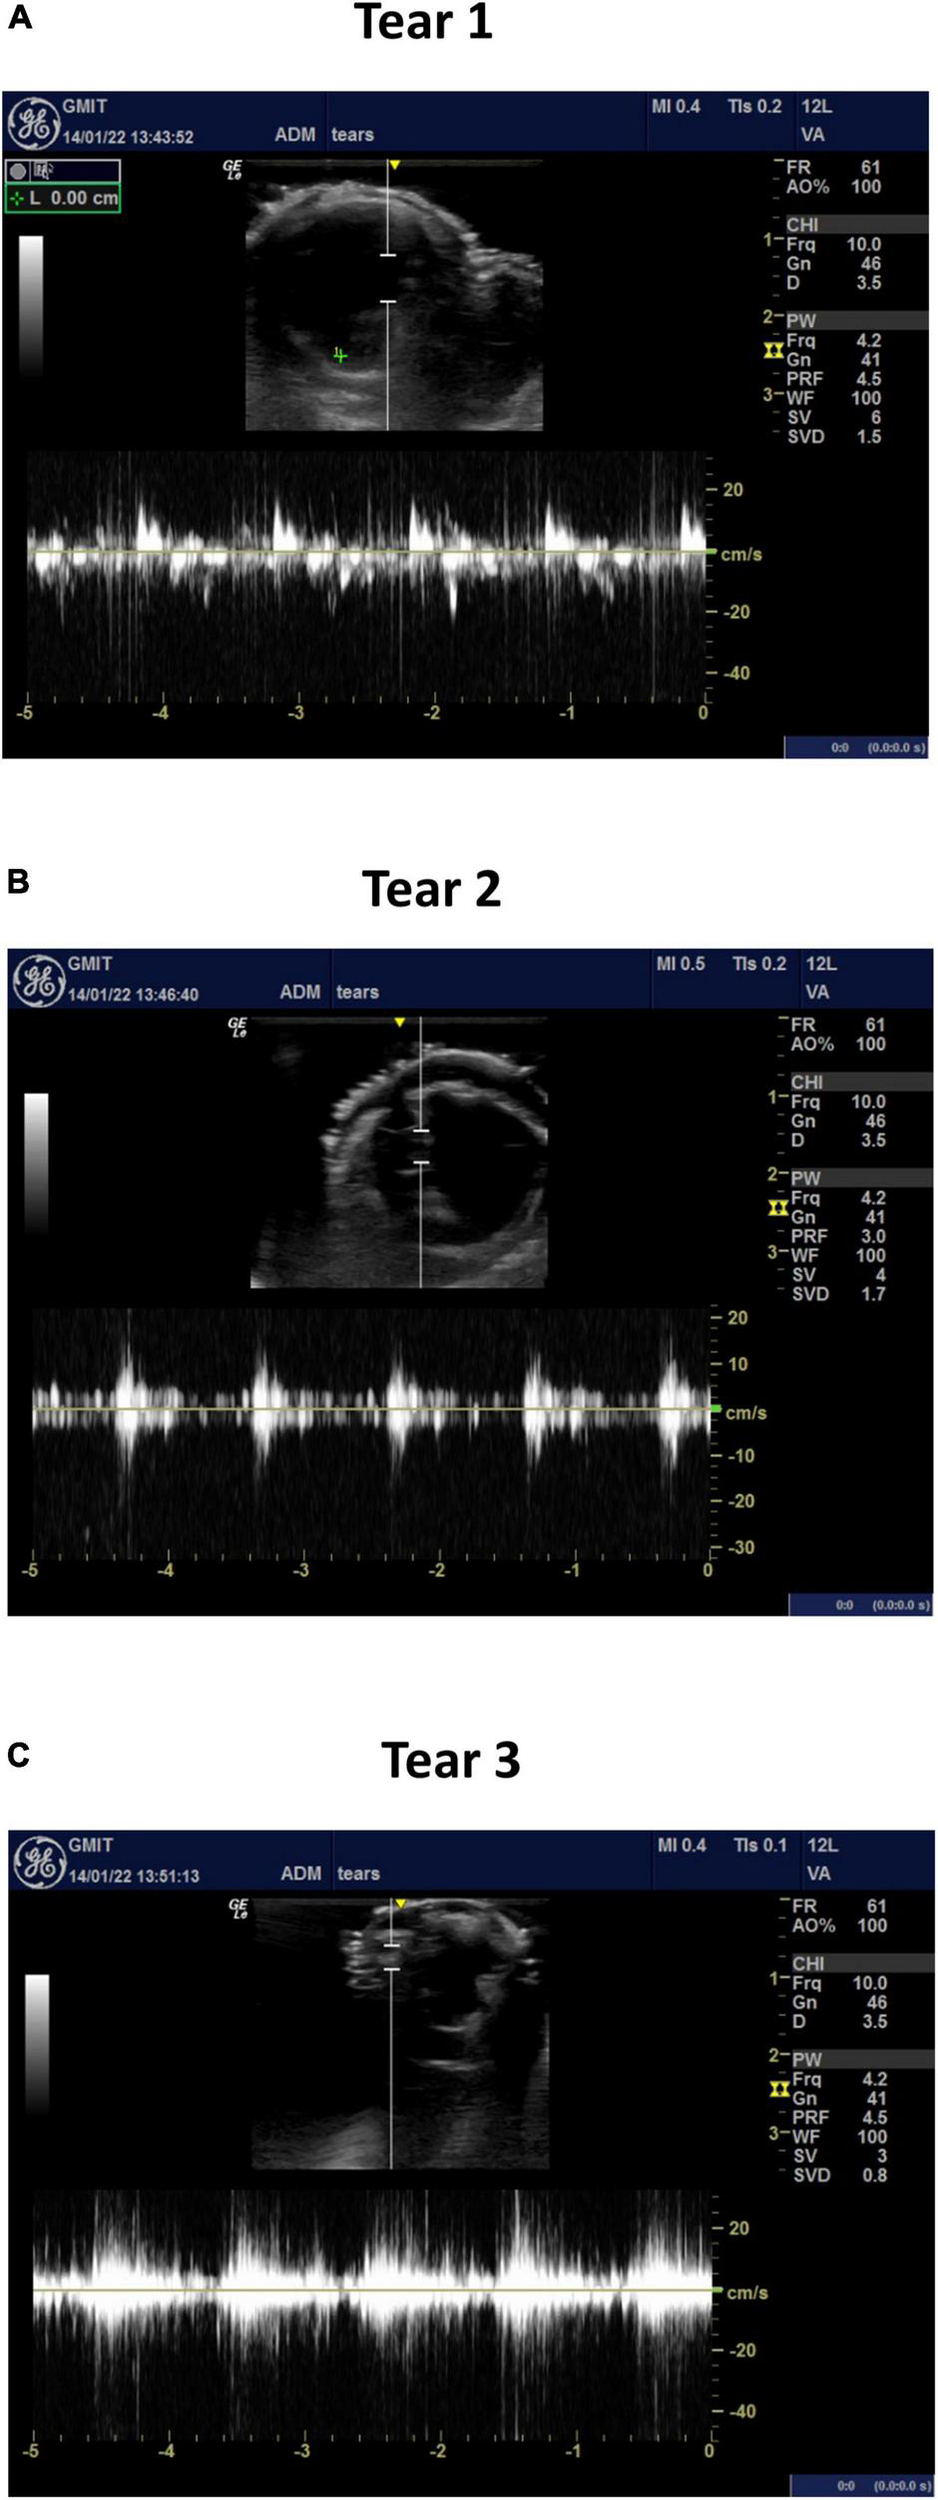

The average velocity profiles measured by the ultrasound machine are shown along three sections of the aortic dissection model (Figure 9) and across the tears (Figure 10). The Pulse Wave Doppler (PWD) mode was applied. The Doppler sample volume (gate) was adjusted to completely encompass the vessel and tears. The Doppler sample volume was positioned parallel to the flow, and the transducer was positioned on the anterior side. The average velocity profiles across the vessels were measured between the first and second tears (Figure 9A), between the second and third tears (Figure 9B), and between the third tear and the iliac vessels (Figure 9C). There was a higher velocity magnitude along the true lumen when compared to the false lumen. The inlet velocities entering the false lumen peaked at ∼15 cm/s (Figure 10A) for the first tear and ∼11 cm/s (Figure 10B) for the second tear and re-entered the true lumen through the third tear with a maximum recorded velocity of ∼11 cm/s. The average estimated flowrates through tears 1 and 2 into the false lumen were 0.08 L/min (2.6% of total inlet flow over one cardiac cycle) and 0.05 L/min (1.6% of total inlet flow over one cardiac cycle), respectively. The peak systolic flowrates entering the false lumen through tears 1 and 2 were 0.25 and 0.1 L/min, respectively.

FIGURE 10

The average velocity profiles measured by PWD across (A) tear 1, (B) tear 2, and (C) tear 3.